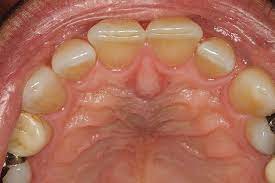

Οι κύστεις αυτές εντοπίζονται εντός του αντίστοιχου πόρου ή εντός των μαλθακών ιστών στη μέση γραμμή της άνω γνάθου, ανάμεσα στους κεντρικούς τομείς, στο στόμιο του πόρου.

Πρόκειται για μια σχετικά συχνή κύστη, που μπορεί να εμφανιστεί κλινικά ως συμμετρική διόγκωση της μέσης γραμμής της υπερώας ή ακτινογραφικά σαν ακτινοδιαυγή περιοχή της μέσης γραμμής. Η πλειοψηφία των περιπτώσεων εμφανίζεται ανάμεσα στην 4η και 6η δεκαετία της ζωής και είναι συχνότερη στους άνδρες με αναλογία 3:1.

Οι περισσότερες περιπτώσεις είναι ασυμπτωματικές, με τη διόγκωση να είναι το κλινικό σημείο που οδηγεί στην αναγνώριση της κύστης.

Επιμόλυνση της κύστης μπορεί να οδηγήσει στην εμφάνιση συμπτωμάτων. Σχηματισμός συριγγίου μπορεί να εμφανιστεί μάλλον στο προέχον σημείο της υπερώιας θηλής.